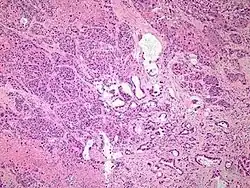

Micrograph of pancreatic ductal adenocarcinoma (the most common type of pancreatic cancer), H&E stain

Histopathology

The most common form of pancreatic cancer (adenocarcinoma) is typically characterized by moderately to poorly differentiated glandular structures on microscopic examination. There is typically considerable desmoplasia or formation of a dense fibrous stroma or structural tissue consisting of a range of cell types (including myofibroblasts, macrophages, lymphocytes and mast cells) and deposited material (such as type I collagen and hyaluronic acid). This creates a tumor microenvironment that is short of blood vessels (hypovascular) and so of oxygen (tumor hypoxia).[2] It is thought that this prevents many chemotherapy drugs from reaching the tumor, as one factor making the cancer especially hard to treat.[2][3]

Pancreatic ductal adenocarcinoma (PDAC) 90% Glands and desmoplasia